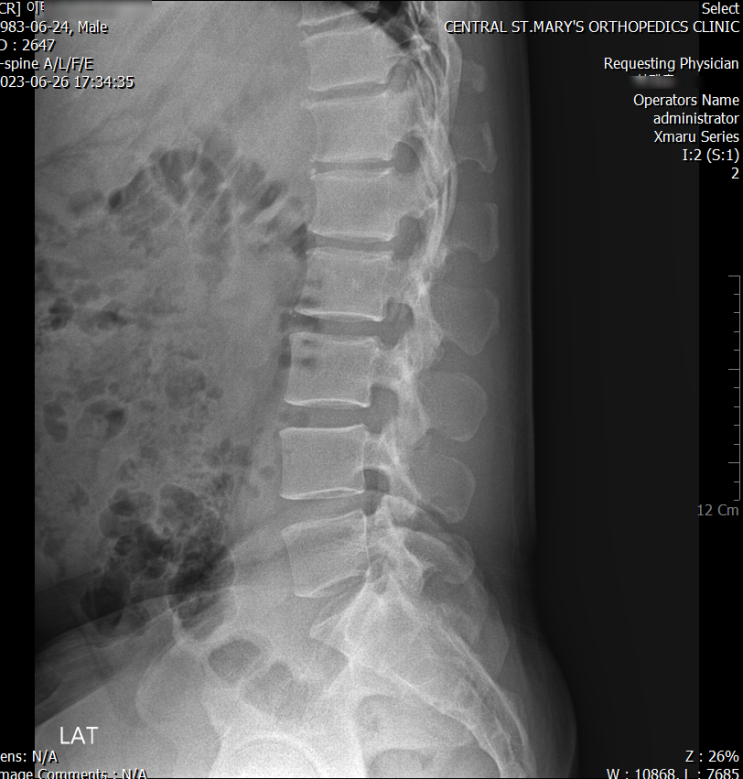

엑스레이상 허리가 일자라고 해서 요추를 frontal 방향으로 밀어줘야 할까?? (X) 40대 남성 사례. lumbar ...